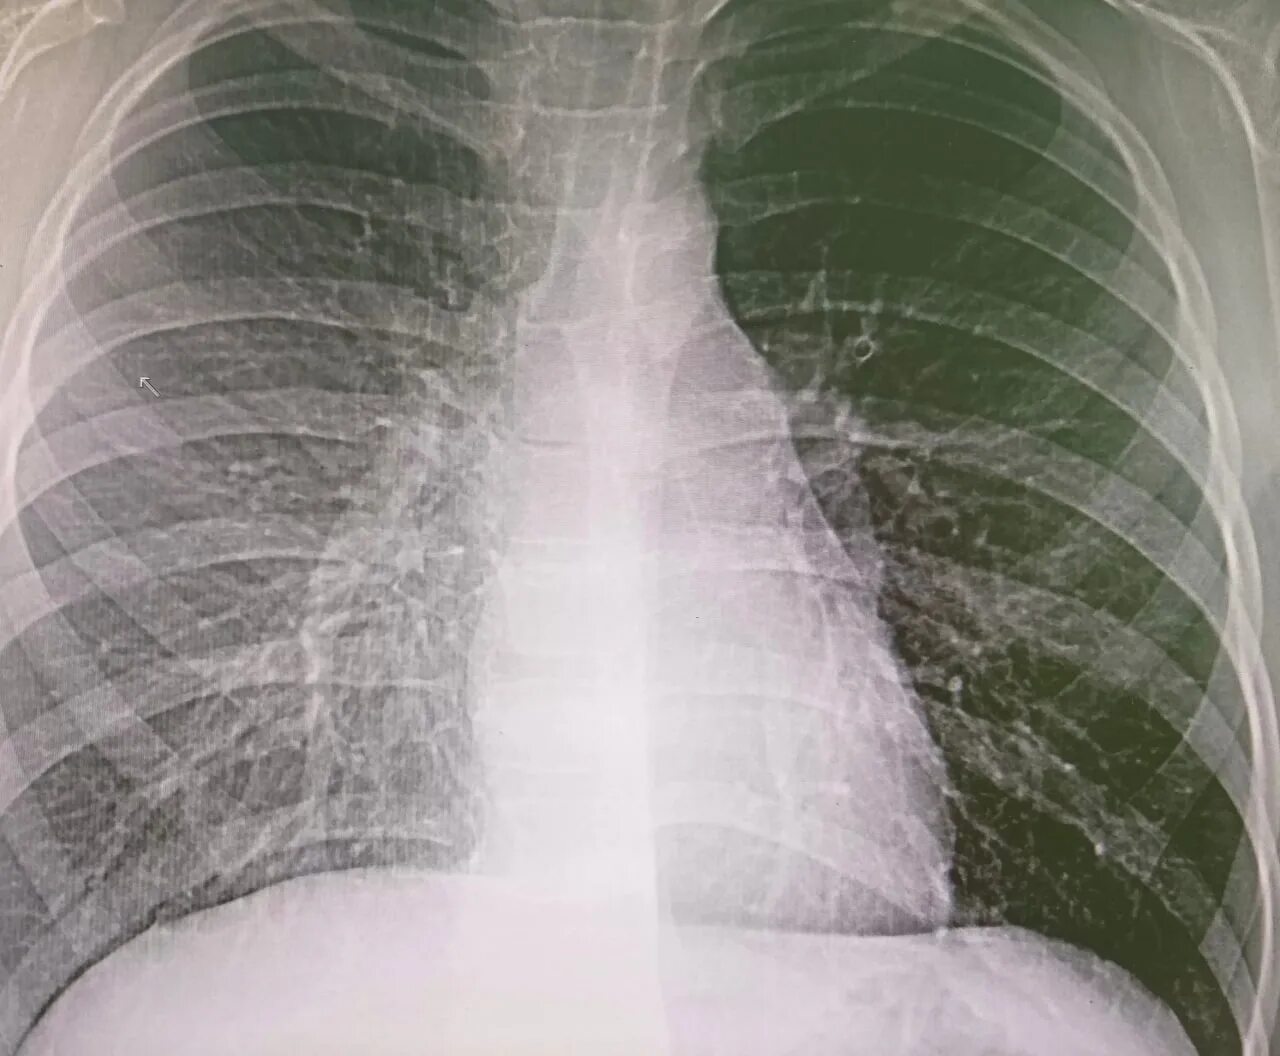

Ренген легких платно